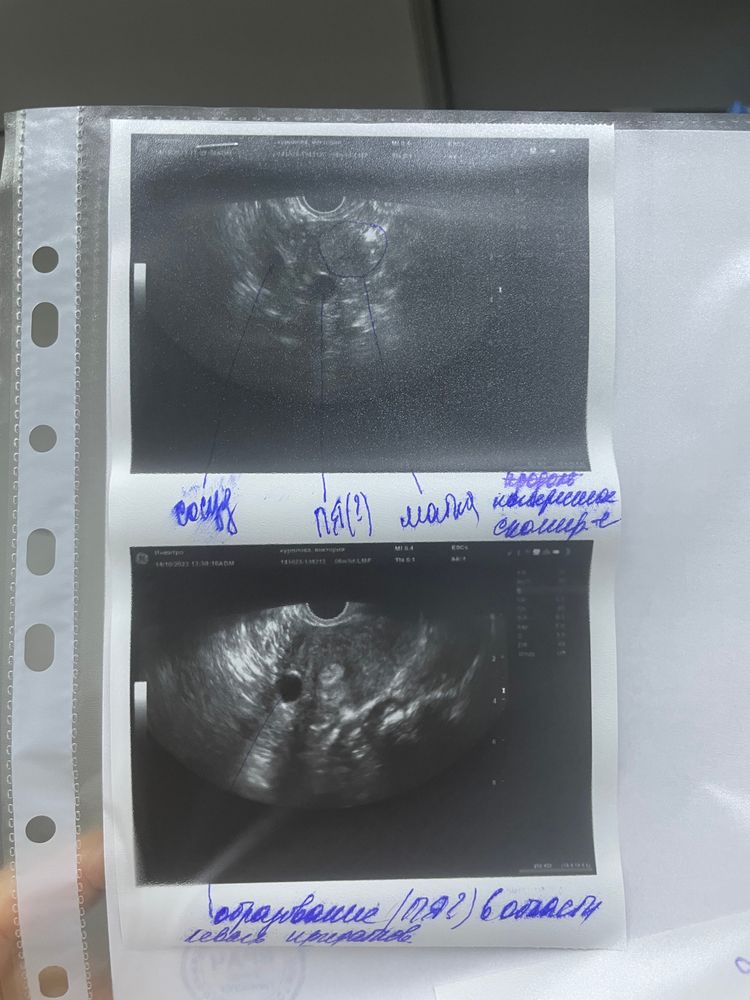

Внематочная под ?

Всем привет, лежу в роддоме с подозрением на внематочную по узи нашли что то похожее на Пя по размерам. Место прикрепления около яичника

Жду завтра снова узи, и врач сказал скорее мы предложим лапароскопию, чтобы разобраться.

Lina , нет, к сожалению снимок на этом узи, это ЗБ, была чистка.